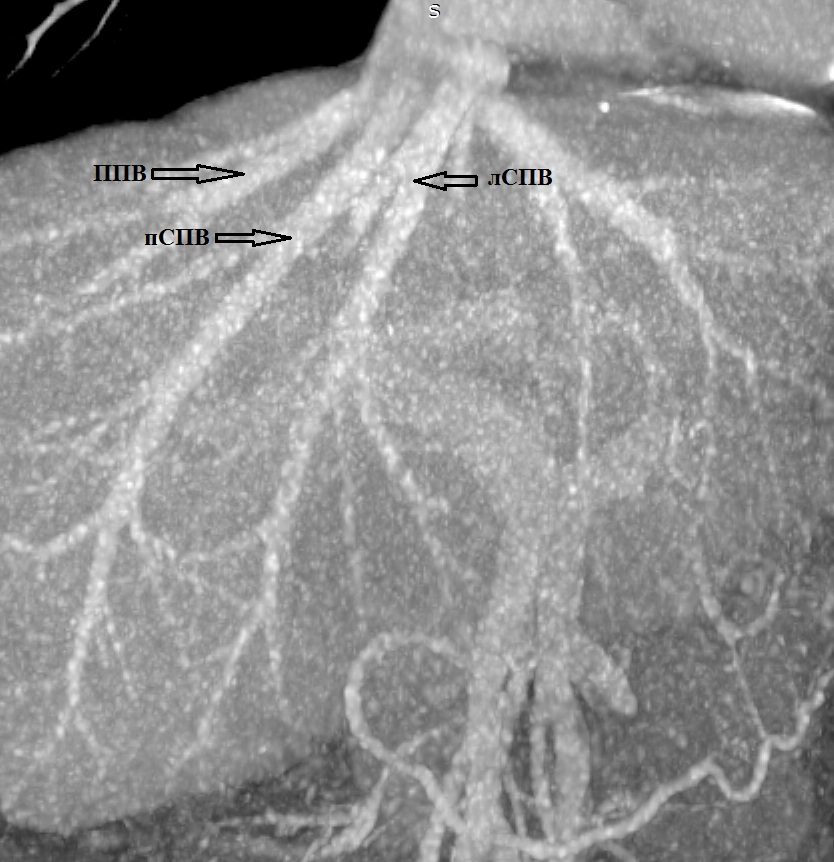

2. Тип А (схема). | |

| Тема | ||

| Тип | Исследовательские инструменты | |

Посмотреть

(1MB)

|

Метаданные ▾ | |